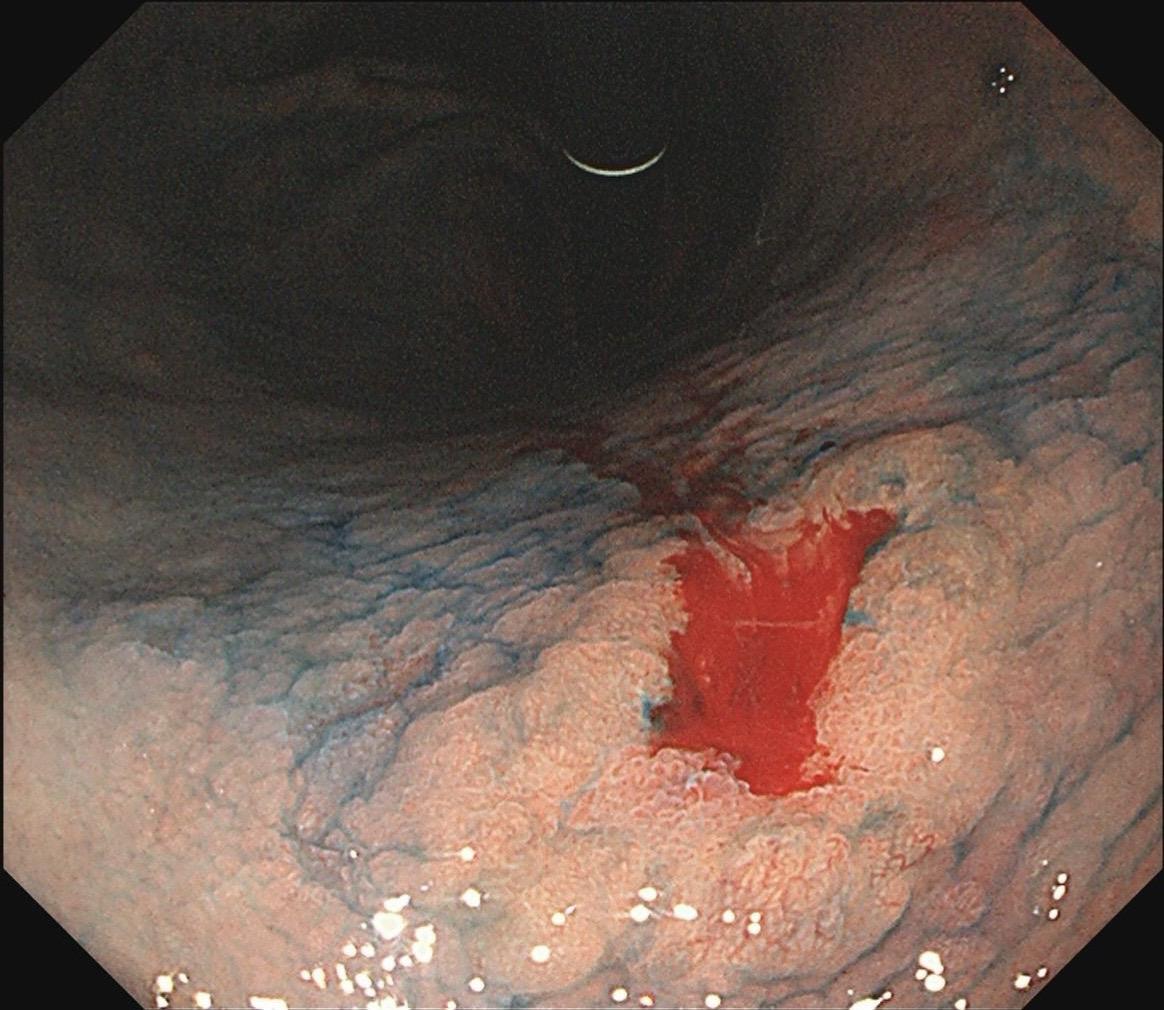

女,57岁,胃角。同事熟人,萎缩背景,色调淡黄,中央浅凹陷,腺管小而密集。